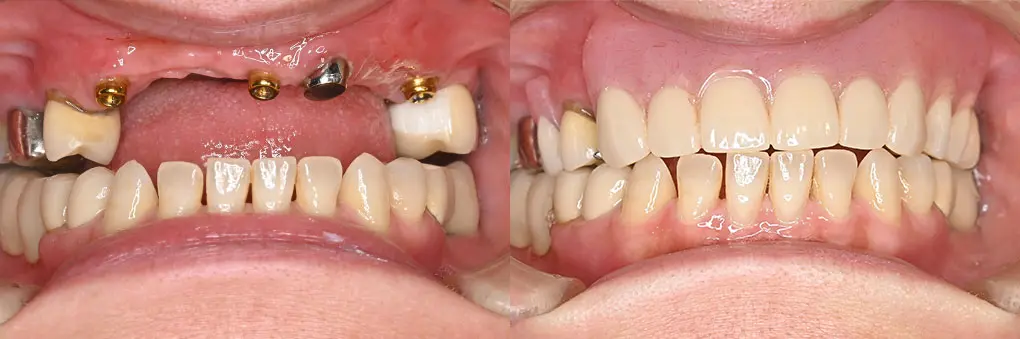

【症例4】入れ歯をインプラントで固定式ブリッジに(40代女性)

| 主訴・背景 | 取り外し式の入れ歯をインプラントで治療したい |

|---|---|

| 診断・治療前の状態 | 抜歯後2カ月のため抜歯窩が存在 矯正治療後前歯部歯根が吸収して、歯の動揺がひどくなり可徹式義歯を装着 |

| 治療方針・計画 | インプラント埋入と同時に骨造成術を併用 |

| 手術・処置内容 | ⚫︎ 治療部位13,11,22 インプラント3本 ⚫︎ 骨造成術を併用治療 ⚫︎ ストローマン社 BL BLT ⚫︎ 上部構造 ジルコニアセラミックブリッジ |

| 治療期間・回数 | 仮歯装着まで2カ月、最終補綴装着まで2カ月、トータル4カ月/6回 |

| 費用・料金(自費診療の場合) | 1,800,000円 |

| リスク・注意点・術後ケア | セラミックの破折、インプラント周囲炎、定期検診 |

| 治療後の状態・経過写真 | 「違和感なく以前の自身の歯よりきれいになりました」 現在、7年経過良好。遠方からの来院のため6カ月定期検診 |

| まとめ・院からのコメント | 学生時代に矯正治療を受け20年後歯の動揺が出現し、近医で抜歯、可徹式義歯装着と失望感が強かった患者様が笑顔になり嬉しく思います。 |